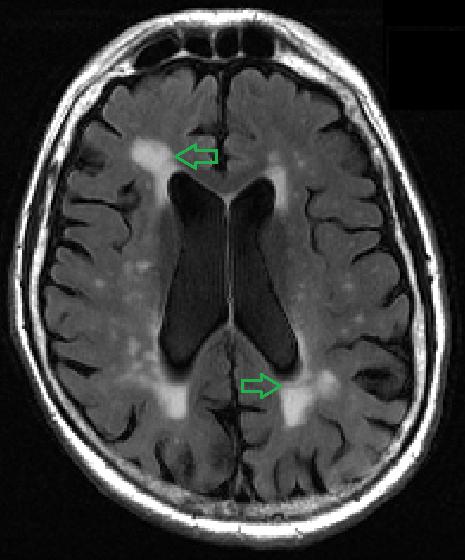

The findings by imaging specialists at NYU Grossman School of Medicine center on small bright spots on scans called white matter hyperintensities. Increased numbers and size of the intense-white spots seen on the mostly gray images of the brain have long been linked to memory loss and emotional problems, especially as people age.

More spots on MRI and their occurrence in the center of the brain have also been shown to correlate with the worsening of dementia and other brain-damaging conditions, such as stroke and depression, say the study authors. The spots represent fluid-filled holes in the brain, lesions that are believed to develop from the breakdown of blood vessels that nourish nerve cells.